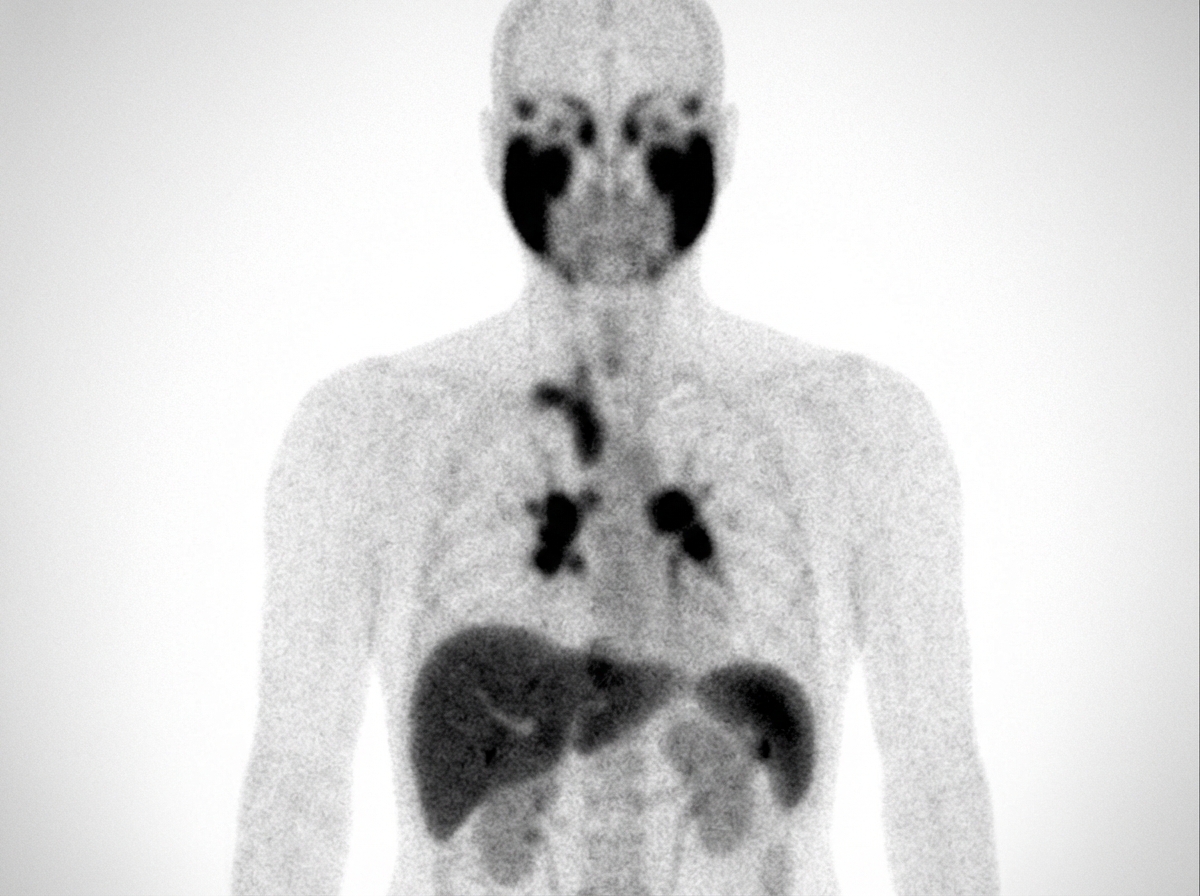

What diagnosis is implied by the results of this gallium scan?

Explanation: ***Sarcoidosis*** - **Gallium-67 scan** shows characteristic **panda sign** (parotid and lacrimal gland uptake) and **lambda sign** (bilateral hilar and right paratracheal lymph node uptake), which are pathognomonic for sarcoidosis. - These specific uptake patterns on gallium scan are highly diagnostic and distinguish sarcoidosis from other inflammatory conditions. *Mumps* - Involves **parotid gland swelling** but lacks the characteristic **bilateral hilar lymphadenopathy** seen on gallium scan. - **Viral parotitis** would not show the **lambda sign** or **systemic inflammatory uptake** pattern typical of sarcoidosis. *Paget's disease* - Primarily affects **bone metabolism** and would show increased uptake in **affected bones** rather than parotid glands or hilar lymph nodes. - **Gallium scan** is not typically used for Paget's disease diagnosis; **bone scan** with technetium-99m is preferred. *Septic emboli* - Would show **multiple scattered hot spots** in lungs corresponding to **infected embolic foci**, not the organized bilateral hilar pattern. - Lacks the characteristic **panda sign** and **lambda sign** that are specific for sarcoidosis on gallium imaging.